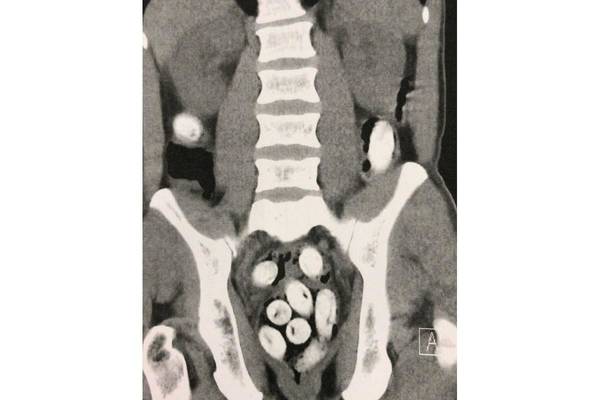

Bereits in der vergangenen Woche deckten Kontrollbeamte des Hauptzollamts Stuttgart am Stuttgarter Flughafen einen Drogenschmuggel mit 250 Gramm Kokain im Körper eines Reisenden auf. Der Mann hatte das Kokain in mehreren Päckchen heruntergeschluckt und reiste anschließend von Lissabon nach Stuttgart. Bei einer Routinekontrolle verstrickte sich der Reisende in Widersprüche und behauptete, in Deutschland nur einen Kurzbesuch machen zu wollen. Als ein Drogenwischtest positiv anschlug, jedoch keine Drogen bei der Kontrolle gefunden werden konnten, hatten die Beamten schnell den Verdacht, dass es sich um einen Körperschmuggler, einen sogenannten Bodypacker, handeln könnte. Zur Überprüfung wurde der 43-jährige in das Krankenhaus Esslingen gebracht, wo eine radiologische Untersuchung den Verdacht bestätigte. Im Anschluss wurden die Drogenpäckchen auf natürlichem Wege ausgeschieden. Zum Glück für den Reisenden waren die verschluckten Päckchen alle unbeschädigt und er hat den Schmuggelversuch zumindest körperlich gut überstanden. Gegen den Mann wurde ein Strafverfahren wegen des Verdachts der Einfuhr von Betäubungsmitteln eingeleitet und er wurde vorläufig festgenommen. Die weiteren Ermittlungen hat das Zollfahndungsamt Stuttgart übernommen, der Mann sitzt in Untersuchungshaft.